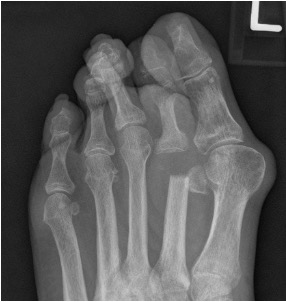

- Excision arthroplasty – risks transfer metatarsalgia and creating an unstable, short toe (Figure 5)

Figure 5: the sequelae of resecting the 2nd metatarsal head